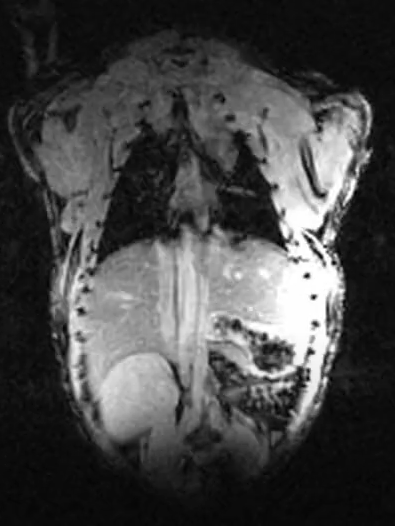

Le Centre abrite le seul appareil d’IRM pour petits animaux à grand champ de la région d’Ottawa (système Discovery MR901 de 7,0 Tesla d’Agilent Technologies / General Electric).

Le Centre abrite le seul appareil d’IRM pour petits animaux à grand champ de la région d’Ottawa (système Discovery MR901 de 7,0 Tesla d’Agilent Technologies / General Electric). Il n’y a qu’environ 10 machines de ce type dans tout le Canada qui offrent une occasion unique de tirer parti de cette ressource et d’obtenir un avantage dans le contenu de votre manuscrit.

Le système d’IRM est équipé d’un aimant supraconducteur à alésage horizontal de 7,0 T et 310 mm de diamètre, interfacé avec la plateforme Signa HDx de General Electric. Le système offre des capacités de recherche préclinique en IRM de haute qualité et robustes avec une variété de contrastes d’imagerie et d’évaluations quantitatives. CIPC fournit un service pour répondre à un large éventail de besoins des chercheurs, de l’imagerie d’animaux vivants aux recherches d’échantillons, la caractérisation d’agents de contraste à la recherche de matériaux et de plantes.

L’imagerie est réalisée à l’aide d’un puissant système de gradient de 300 mT/m (30 Gauss/cm) (diamètre intérieur de 210 mm) équipé d’une capacité de cale d’ordre 2. Une large gamme d’antennes de radiofréquence (bobines) sont disponibles, allant des antennes de corp aux antennes de réception dédiées et activement découplées pour le cerveau de souris et de rats. Des systèmes de surveillance physiologique et de manipulation des animaux sont également disponibles. Le spectromètre IRM est équipé de capacités X-nuclei.